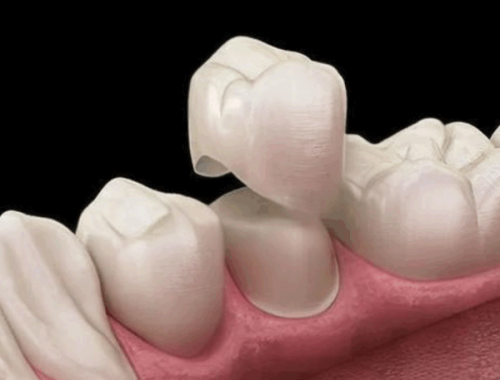

刚走进医院,就被那里温馨舒适的环境吸引了。工作人员热情地接待了我,引导我完成各项检查。李胜刚医生仔细地查看了我的牙齿情况,根据我的口腔状况制定了详细的金属托槽矫正方案。他耐心地给我讲解矫正的过程和注意事项,让我对整个矫正过程有了清晰的了解。

在安装金属托槽的过程中,李医生的操作非常熟练和细致。他一边操作一边和我聊天,缓解我的紧张情绪。虽然安装托槽的时候稍微有点不舒服,但我知道这是迈向整齐牙齿的必经之路。安装完成后,李医生还反复叮嘱我一些日常的护理方法,比如如何正确刷牙、饮食上需要注意什么等等。